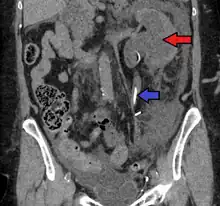

- Stone causing hydronephrosis[16]